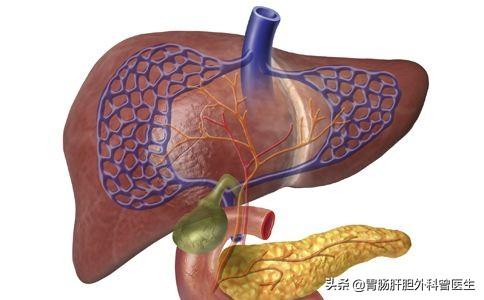

Les kystes hépatiques peuvent être classés cliniquement en deux types, à savoir les kystes cholédociens simples (polykystiques) et les kystes hépatiques polykystiques.

I. Kystes hépatiques simples (polypoïdes)

Les kystes hépatiques simples sont rares avant l'âge de 40 ans et augmentent fortement après cet âge, et en termes d'incidence, ils sont plus fréquents chez les femmes que chez les hommes.

Ce type de kystes hépatiques, qui sont des lésions bénignes, ne présentent généralement pas de symptômes cliniques évidents et ne sont découverts qu'accidentellement lors d'une échographie ou d'un examen par tomodensitométrie, et seuls certains kystes de grande taille, qui provoquent des douleurs abdominales ou une gêne abdominale chez les patients, sont également généralement féminins.

II. le foie polykystique

Le foie polykystique en tant que maladie génétique congénitale.Depuis que je suis enfant.,non récurrentPolykystose rénale combinée。